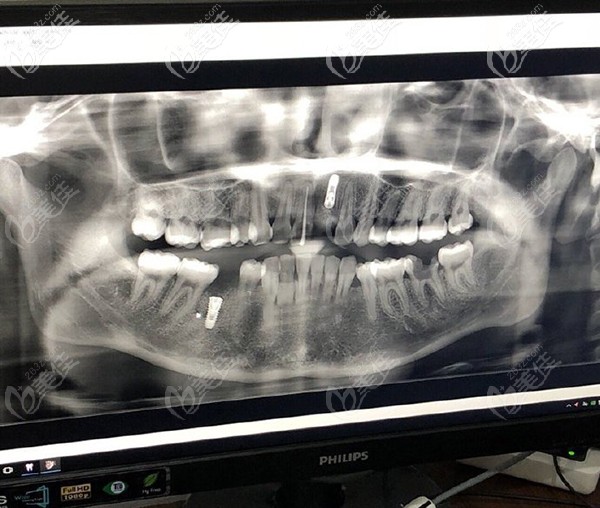

問題是本寶寶還不止缺一顆牙,只不過在我看來門牙尤為重要,來院后,醫(yī)生大概看了牙齒情況后,建議還是拍個CT看看,以便于確認給我更好的方案。

放大看看更清楚

【牙齒情況】:門牙缺失一顆,下半口缺失一顆,但是有殘根。